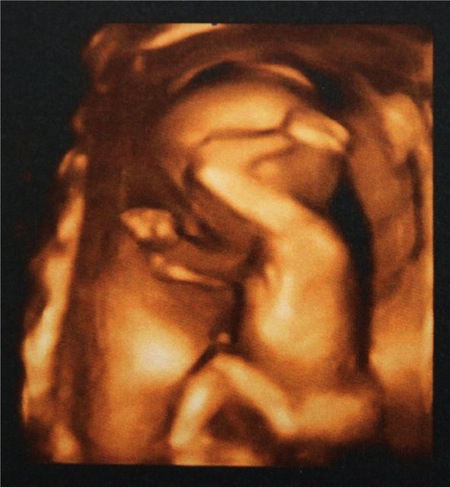

А у нас МАЛЬЧИК!

Мы сегодня с мужем были на 4Д узи и узнали, что у нас будет МАЛЬЧИК!!!!! Все думали, что будет девочка, а оказался сюрприз!))